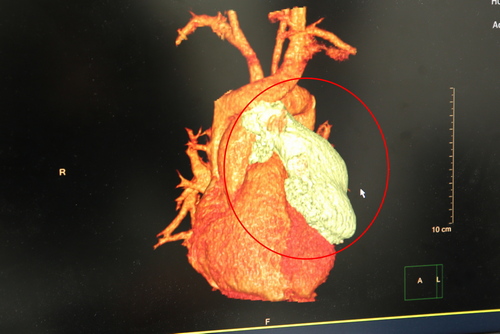

張睿智主任表示,經過電腦斷層掃描後,陳先生的腫瘤為八公分大的胸腺瘤,形狀如雞蛋,不僅離心包膜、血管非常近,執行手術有一定的難度,所以使用達文西手術為陳先生移除腫瘤過程中須小心翼翼地先將前縱膈腔的腫瘤與血管分離,再將腫瘤完整清除乾淨。

紅圈處為陳先生的胸腺瘤,已有八公分大,腫瘤非常靠近心包膜與血管  紅圈處為陳先生的胸腺瘤,已有八公分大,腫瘤非常靠近心包膜與血管